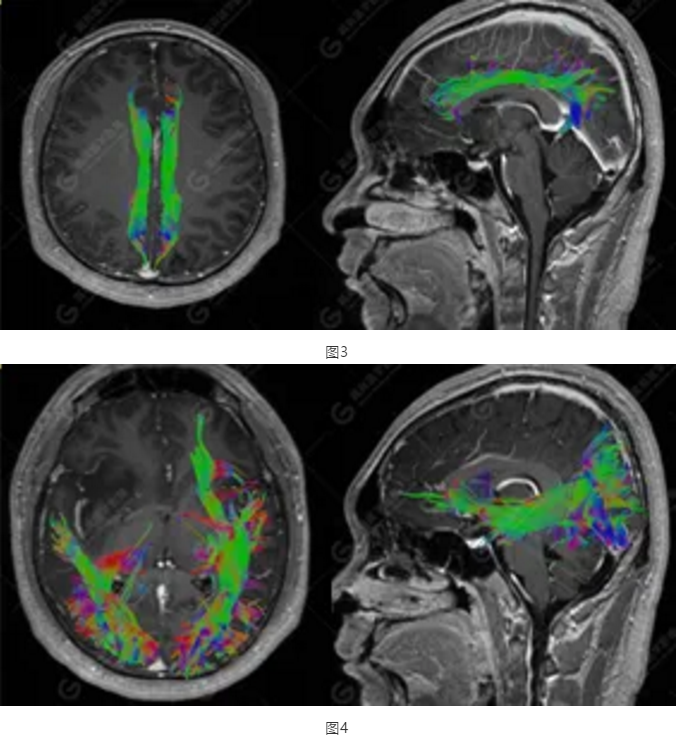

以上為DTI成像,圖1為皮質(zhì)脊髓束,圖2為胼胝體束,圖3為扣帶回束,圖4為額枕束。DTI成像示右側(cè)額枕束前部明顯受壓、部分未見(jiàn)顯示;胼胝體束、雙側(cè)扣帶束、皮質(zhì)脊髓束及左側(cè)額枕束形態(tài)可,纖維束未見(jiàn)明顯破壞,未見(jiàn)明顯稀疏減少。